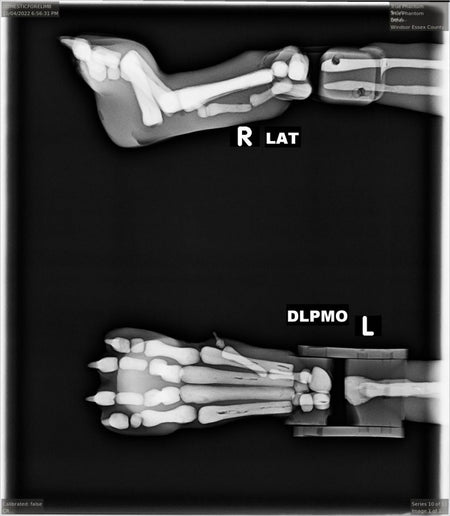

The dog phantom has accurate anatomical structures and removable body parts(head, limbs, torso, and tail). This aids in performing various positioning techniques under the Ultrasound, X-RAY, CT, and MRI imaging modalities.

- Arm (Humerus)

- Elbow joints

- Forearm (Radius, Ulna)

- Paw (wrist with fingers)

- Paw (Finger bones)